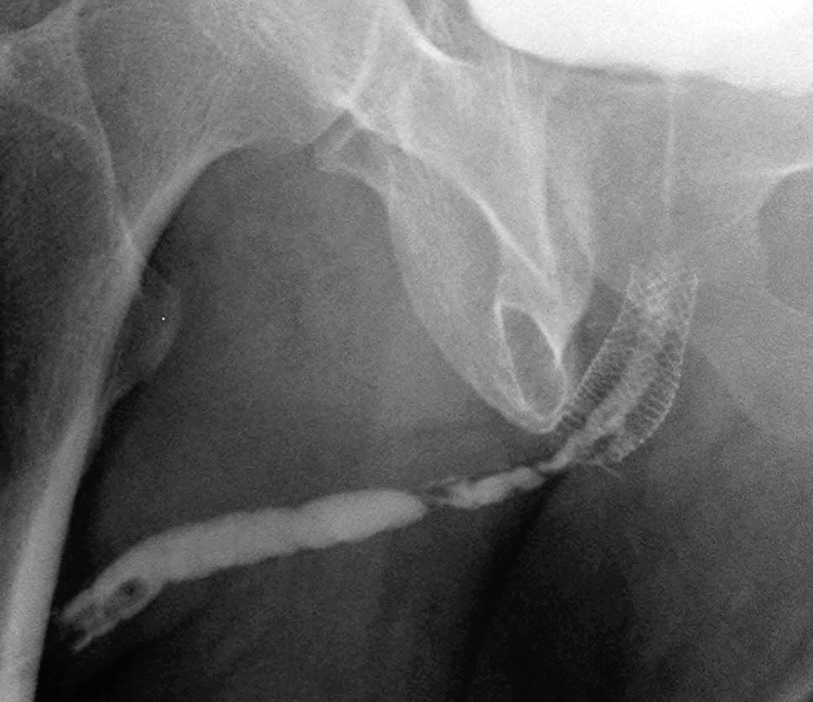

3.0 cm UroLume stent with severe distal urethra restenosis in a patient performing long-term auto-dilatation before definitive stent removal and urethral reconstruction